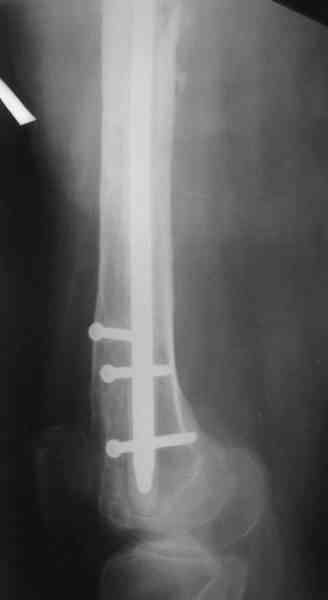

1, 2, 3, 4 - рентгенограммы бедра от 8 августа этого года (через четыре месяца после операции);

4, 5, 6 - рентгенограммы бедра и фотографии пациентки (прошу прощения за низкое качество рентгеновских снимков) от 7 сентября 2007 г.